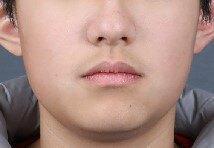

治疗后

- 治疗后2年

通过隐形矫治,序列化推上牙列向后,并适量扩弓,排齐内收上前牙,适量唇倾和片切排齐下前牙。

配合二类牵引,实现咬合跳跃,改善侧貌。